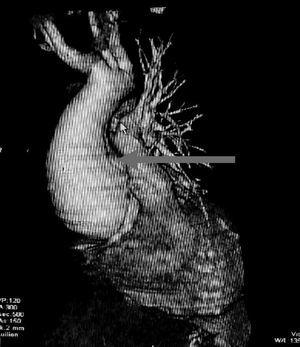

Figura 1. Angio TAC con reconstrucción 3D mostrando la dilatación aneurismática del tracto de salida de la aorta.

Presentamos el caso de un hombre de 33 años, sin antecedentes médicos de interés, que ingresa en la Unidad de Cuidados Intensivos (UCI) procedente de otro centro hospitalario por insuficiencia cardíaca congestiva y fallo multiorgánico. El paciente refería un cuadro subagudo de fiebre y dolor torácico no continuo que mejoraba con ciertas posturas y que se acompañaba de tos, expectoración hemoptoica y disnea. En la exploración se apreció hipotensión arterial y taquicardia de 170 latidos por minuto (lpm) con ritmo de galope y crepitantes bilaterales. Se realizó una ecocardiografía transtorácica comprobándose una fracción de eyección del ventrículo izquierdo muy deprimida con alteraciones de la contractilidad segmentaria anteroseptal, lateral y discreto derrame pericárdico. Con el diagnóstico de miopericarditis fue remitido a nuestro servicio donde se repitió la ecocardiografía, apreciándose una gran dilatación del tracto de salida del ventrículo izquierdo compatible con disección aórtica. Para confirmar el diagnóstico, ante la existencia de estigmas marfanoides, se realizó una tomografía axial computarizada (TAC) helicoidal con reconstrucción en 3D, comprobándose una disección aórtica tipo A que interesaba a los troncos supraaórticos (fig. 1). Tres días después del diagnóstico y ante la grave disfunción ventricular se sometió al paciente a un trasplante ortotópico cardíaco con reparación atípica de la aorta (fig. 2, durante el acto quirúrgico). Una semana después fue dado de alta de nuestro servicio sin incidencias.